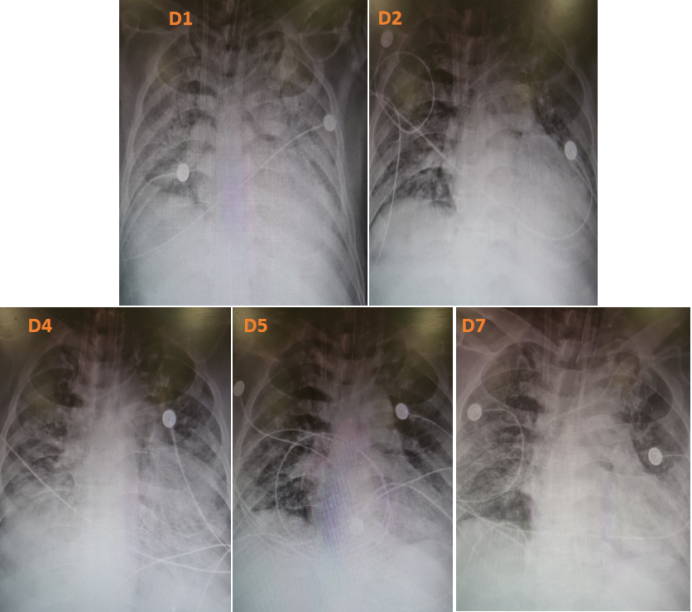

1天7天的胸片动态监测可见肺部病变呈逐步吸收好转趋势(图2)

图片

2  患者胸片变化